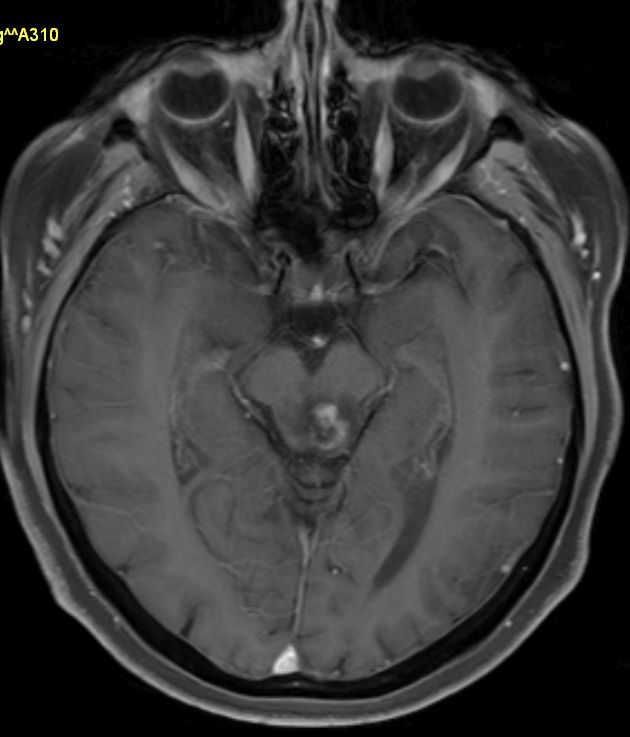

Vierhügelplatte 66-jährige Frau mit Sehstörungen, Ptose rechts mehr als links, Gehörverschlechterung und Gleichgewichtsstörungen. Stereotaktische Biopsie: Astrozytom Grad 3 (Grad unsicher).